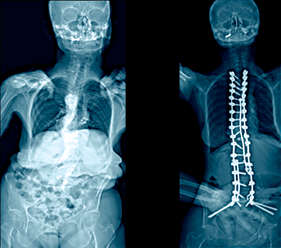

A patient presented with severe kyphosis due to multilevel osteoporotic compression fractures. She was treated with posterior spinal instrumentation and fusion from T2-sacrum with a T11 vertebral column resection in a nine-hour surgery.